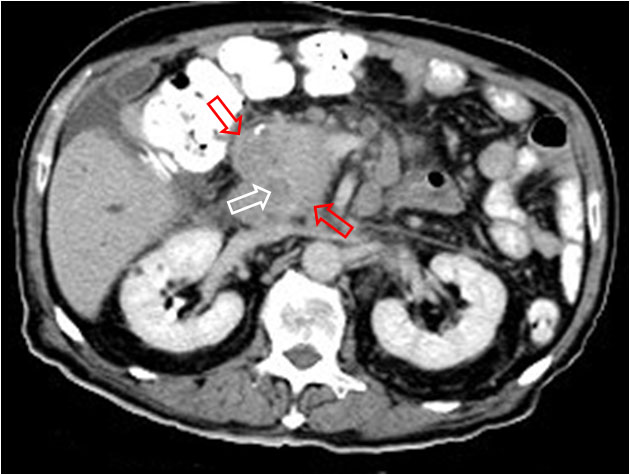

SIGNO DE LA ESCOPETA o CANAL PARALELOescopeta1Signo clásico en ecografía de dilatación de la vía biliar intrahepática. Un conducto biliar dilatado –flecha roja- corre paralelo a la rama portal acompañante –flecha blanca-, con calibre similar, dando una imagen de escopeta de doble cañón.escopeta2Corte axial de TC de abdomen del mismo paciente, que muestra dilatación biliar intrahepática donde puede verse una imagen similar al signo ecográfico (círculo).escopeta3Un corte más caudal muestra una masa en la cabeza del páncreas (flechas rojas) causante de la dilatación biliar (flecha blanca).